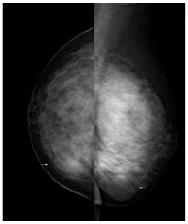

【摘 要】目的研究乳腺叶状肿瘤的临床与分析.方法采用光镜复习原理诊断乳腺叶状肿瘤,从而按良性诊断的方法从中分析.结果32例乳腺叶状肿瘤的患者有超过一半的为良性肿瘤,恶性和交界性的肿瘤只占很少数.结论乳腺叶状肿瘤的预后护理与临床手术方法有着密不可分的联系.

乳腺叶状肿瘤是目前乳腺所有肿瘤中占比率最小的,这种肿瘤易发年龄在30~50岁.乳腺叶状肿瘤的组织内构比较像叶子的形状,细长间隙小,乳腺叶状肿瘤的名称和诊断标准还没有得到一致,常常医生检查出的恶性肿瘤判定为囊肉瘤,然而却把较小的细胞异性称为纤维腺瘤.因为还没有统一的命名和治疗诊断的标准,导致医生在治疗和诊断上受到了阻碍,有些检验项目无法进行.现在WHO已经明确了该类肿瘤的归属,统一为叶状瘤,但是包括了良性、交界性、恶性三种[1].叶状瘤的良性诊断一般都是采用Azzopardi和Salvadori中的标准值进行检查.通过对病例进行研究后得出的结论,分析该类肿瘤的手术方式和病症对预后的影响,从而为临床收集数据,方便以后治疗,现做出如下总结.

从2000年1月~2010年12月来进行检查的32例患者中,有20例患者检查诊断为良性的肿瘤,5例患者诊断为交界性的肿瘤,7例患者为恶性肿瘤.这些患者的年龄平均在48岁,患有的肿瘤大小各不相同.通过对这些肿瘤的病理进行切片研究,按照Azzopardi和Salvadori的诊断标准,研究其中的数据,包括肿瘤周围的组织形态和细胞的间隙、肿瘤是否坏死等病症的出现,相对于肿瘤的不同,对待检查方法方式也不相同,还是要以主要的范围进行分析治疗.

32例患者中,良性患者相对于交界性和恶性肿瘤的占有比率较大,良性肿瘤发病的年龄一般在35岁,肿瘤的一般都是4cm左右;交界性肿瘤的发病年龄一般在45岁上下,肿瘤的大小在6.1cm左右;而恶性肿瘤的发病年龄稍稍会大一些,在51岁左右,肿瘤的大小在8cm.良性肿瘤的发展扩大很快,如果发现及时进行切除手术,如果单纯的处理肿块,1年内还会出现复发的可能,复发后还要再一次的进行切除手术.局部扩大的患者采用全部切除的手术方法,手术后复发的可能性相对很小.无论是良性还是交界性肿瘤的患者采取